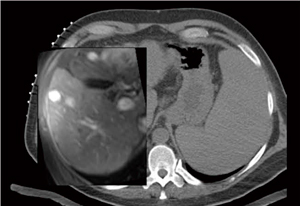

図1 CT誘導下肝がん焼灼術における術中CTと術前MRIの変形統合 (慶應義塾大学およびハーバード大学: 小黒先生提供)

図1 CT誘導下肝がん焼灼術における術中CTと術前MRIの変形統合

(慶應義塾大学およびハーバード大学: 小黒先生提供)